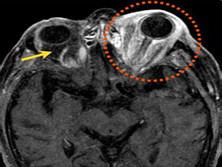

眶骨髓炎(眶骨髓炎)

眶骨髓炎(orbitalosteomyelitis)是一种少见的眼眶炎症,可发生在任何年龄,但儿童易患此病可能与其免疫功能尚不完善,易患上呼吸道感染有关。眶上壁是最常见的发病位置,其次为眶外壁,而眶下壁和内壁很少受累。